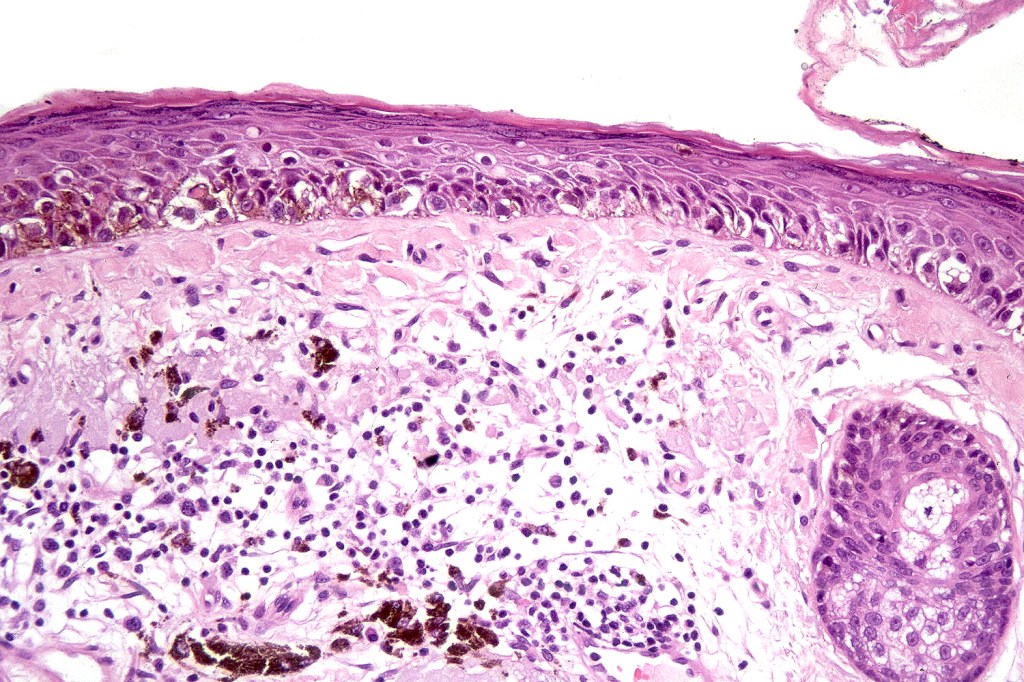

•Epidermal atrophy & solar elastosis

•Atypical melanocytes located predominantly along the basal layer of the epidermis, singly, in short arrays or extensively involving the whole epidermis

•Adnexal involvement

•Dense melanin pigmentation may affect the whole epidermis making it difficult to determine which cells are melanocytes & which are keratinocytes! DAB-lablled antibodies should be avoided as they can be impossible to interpret

•Dermal melanophages & lymphocytic infiltration